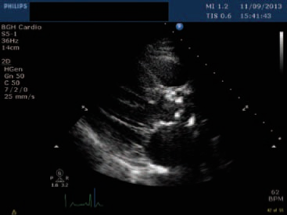

First-line: non-invasive gold standard:

Echocardiography and Doppler: A narrow AV is diagnostic; mean pressure gradient and jet velocity across the valve.